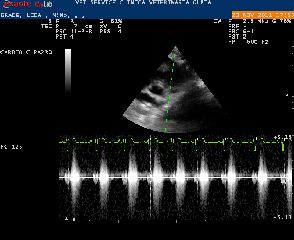

Carissima Cosetta, questa mattina abbiamo portato Greta dal dott. Santilli per capire cosa è possibile fare per la sua delicata situazione.

Dopo aver eseguito un ecocardio il dott. Santilli ha subito notato un peggioramento della condizione della cagnolina.

La stenosi polmonare di Greta è di tipo misto nel senso che oltre ad interessare il ventricolo, interessa anche l'arteria: ventricolo e arteria assumono una forma cosiddetta a "clessidra", ostacolando molto il corso della circolazione sanguigna.

Il dott. Santilli pertanto sconsiglia un nuovo intervento poiché l'utilizzo del palloncino potrebbe danneggiare l'arteria provocando una emorragia che sarebbe fatale per la cagnolina.

La decisione di non intervenire quindi ci è parsa la più sensata.L'operazione, nel caso dovesse riuscire, migliorerebbe di pochissimo la situazione con la probabilità di una recidiva, mentre, lasciando le cose come stanno,Greta potrebbe vivere, con opportuni accorgimenti e attento supporto medico, una vita tranquilla e di discreta qualità.

Il dott.Santilli ci ha fatto esempi di cagnolini come Greta che hanno avuto una aspettativa di vita discreta pur non potendo ambire alla durata di vita media di un cane sano.